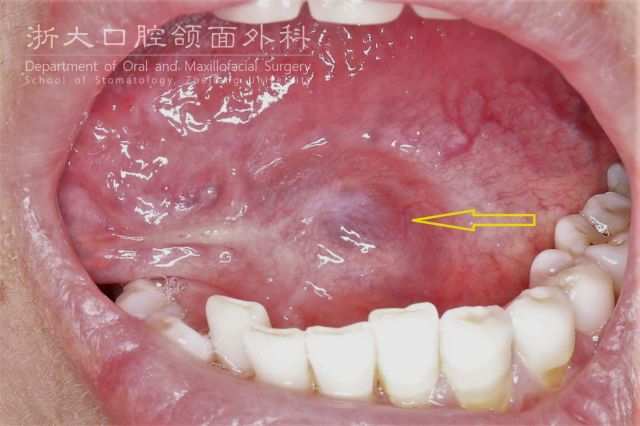

舌下腺管细小,容易因炎症、结石、损伤等因素而引起缩窄、阻塞、分泌物外渗,形成舌下腺囊肿。感觉就像口底起了一个水泡一般的疙瘩,不痛;当疙瘩变大时可将舌头顶起来,可能影响咀嚼,说话含糊不清。水泡呈淡蓝紫色,柔软,用手按压时能感觉到液体在流动,破溃后会有鸡蛋清样黏稠液体流出,有时略带黄色。

向左滑动查看舌下腺囊肿图片

有时,舌下腺囊肿会“调皮”地穿过口底肌群,进入颌下区,感觉一侧出现了双下巴,这就是舌下腺囊肿的口外型口外型舌下腺囊肿穿刺可见淡黄色黏稠液体,可拉丝。

口外型舌下腺囊肿穿刺可见淡黄色黏稠液体,可拉丝